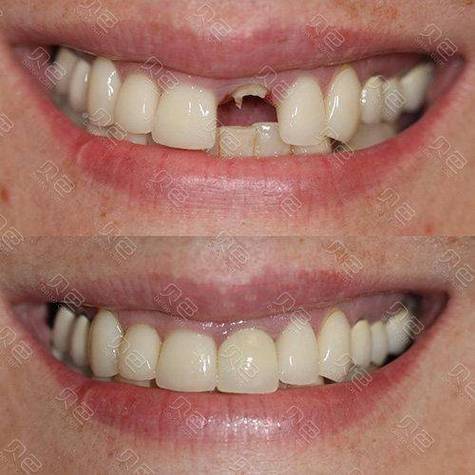

种牙和整牙同时进行,是近年来口腔医学中针对特定患者群体提出的联合治疗方案,旨在解决牙齿缺失与排列不齐并存的问题,缩短治疗周期,提升功能与美学效果,这一方案并非适用于所有人,需严格评估口腔条件,但合理实施下能实现“1+1>2”的治疗效益。

优势:缩短周期,提升综合疗效

- 功能与美学协同:正畸过程中可动态调整种植体位置,使牙冠与邻牙排列更协调;种植体早期植入可防止缺牙区牙槽骨进一步萎缩,避免后期正畸后“黑三角”或牙龈凹陷;